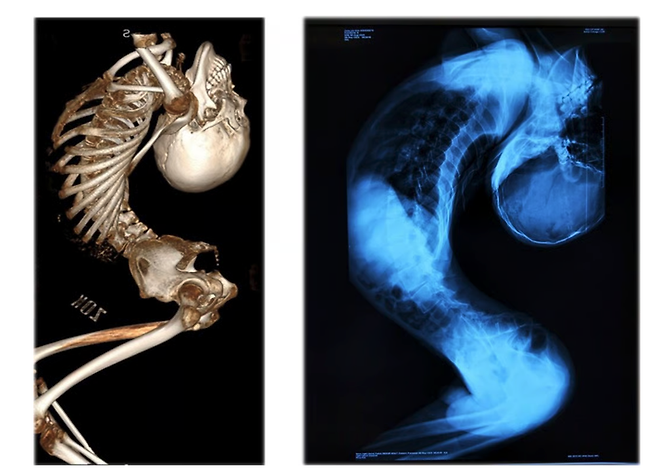

하루 평균 6시간 재활 훈련 이어가

180도로 꺾인 허리로 인해 '폴더 소년'으로 불리던 중국의 장옌천이 마침내 똑바로 서는 데 성공했다. 지난 25일 홍콩 매체 사우스차이나모닝포스트(SCMP)는 장옌천이 최근 진행한 생중계에서 처음으로 곧게 선 채 걸음을 내디뎠다. 중국 산둥성의 작은 마을에서 자란 그는 목이 점점 뒤로 꺾이며 몸이 알파벳 'Z'자 형태로 접혀 갔다. 곧게 서려 해도 키는 120㎝에 불과했고, 자연스럽게 서 있으면 80㎝ 정도에 그쳤다.

세계 최초 180도 척추 교정 수술 성공 사례2024년부터 장옌천은 척추 기형 치료로 유명한 량이젠 교수의 치료를 받기 시작했고, 올해 6월 마지막 수술을 마쳤다. 그는 지난 2년간 허리뼈, 경추, 고관절, 흉부 뼈를 절단 후 재정렬하는 네 차례의 초고난도 수술을 받았다. 전신 마비나 사망 위험이 따르는 극도로 위험한 수술이었지만 성공적으로 끝나 그는 곧바로 침대에 똑바로 누울 수 있었다. 의료진은 이를 "세계 최초의 180도 척추 교정 수술 성공 사례"라고 발표했다.